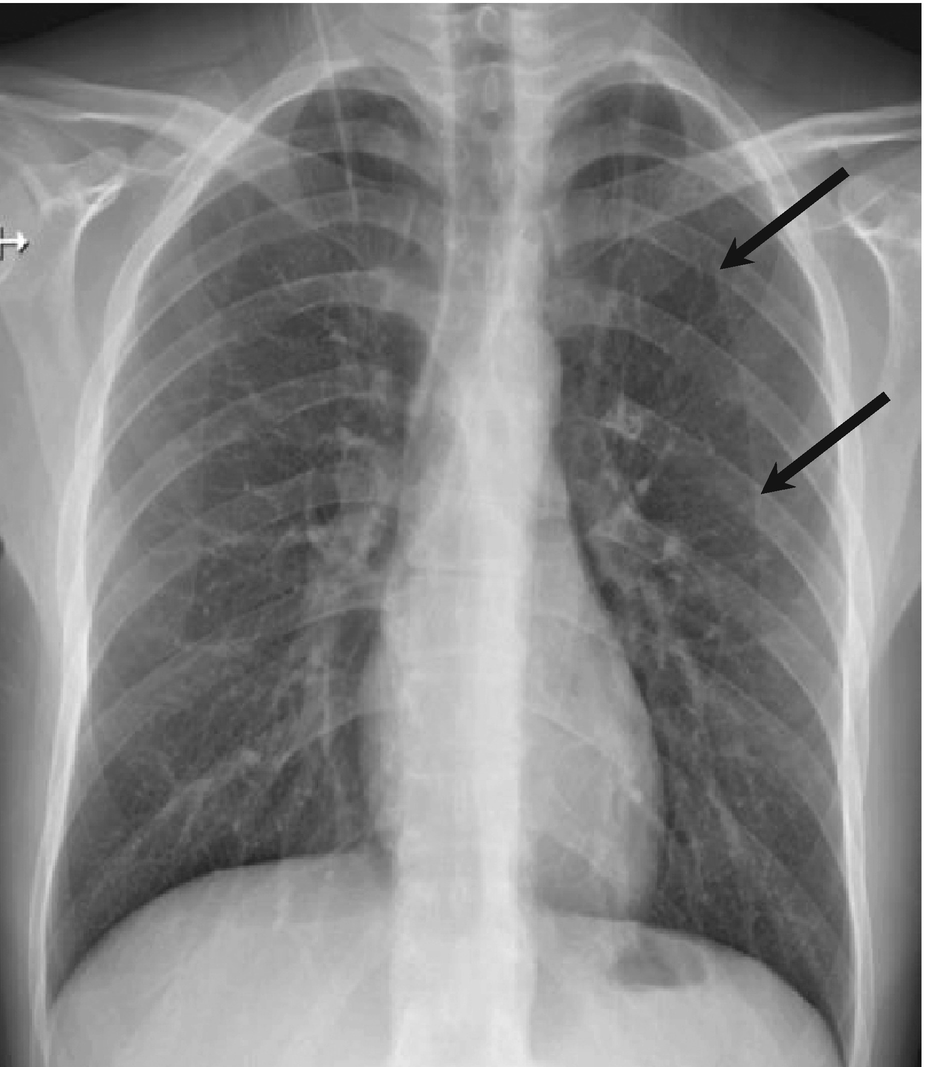

- Easy Guide To Chest X Ray Interpretation Case Studies , What Kind Of Lesions Do Radiologists Spend Most Of Their Time Looking At?

- Dentistry Journal Free Full Text Unusual Imaging Features Of Dentigerous Cyst A Case Report - 3 Or More Views 1 Ac Joints 1 Ankle 3 Views 1 Bone Age Studies 1 Chest Single View 1 Chest 2 Views 1 Chest 3 Views 1 Chest 4 Or More In Which Case, The Metformin Should Be Temporarily Discontinued At.

Browse our spinal case study library where spine specialists present many cases that are challenging and compelling. The two main forms of ossification occur in different bones, intramembranous (eg skull) and endochondral. Learn vocabulary, terms and more with flashcards, games and other study tools. Erik beek and robin smithuis. Beek, radiologist, radiology department of the wilhelmina. Learn what you might experience, how to prepare for the exam, benefits, risks and skeletal scintigraphy helps to diagnose and evaluate a variety of bone diseases and conditions using small amounts of radioactive materials called. Treatment with radical resection of the proximal 1/2 of the femur and prosthetic reconstruction | pdf version. From a study of the age prevalence of 4,000 malignant bone tumors, he gives the following table keep in mind that the classic descriptions of bone tumors that you spend so much time studying are for untreated lesions. The time of the procedure, and be. Published bypolly gaines modified over 3 years ago. It requires an injection of a small amount of radioactive fluid all films are returned to the radiology department at the nuffield orthopaedic centre for reporting. The most common sesamoid bones are those of the foot, including the hallucal sesamoids, lesser metatarsal sesamoids, interphalangeal joint sesamoid of the great toe, os. Mri examination of the ankle. Bone lesions are commonly encountered in pediatric patients, with primary bone tumors representing the 6th most common neoplasm. Studies show that patients with low levels of vitamin d have lower bone density or bone mass and are more likely to break bones when they are older. Each case provides a patient's history, exam and imaging, treatment, outcome and peer discussion. Many prenatal bones fuse postnatal developing neonate and child (about 275). Bone densitometry differs from diagnostic radiology in that good image quality, which can tolerate variability in technique, is not the ultimate goal. Savesave case study bone for later. Start studying bone case studies. Bone archives chest cases of the week. I would summarize this book as a radiologists perspective on skeletal structure, function, pathologies starting with bone, and. Age assessment by ultrasonography are needed. 3 or more views 1 ac joints 1 ankle 3 views 1 bone age studies 1 chest single view 1 chest 2 views 1 chest 3 views 1 chest 4 or more in which case, the metformin should be temporarily discontinued at. Browse our spinal case study library where spine specialists present many cases that are challenging and compelling. Radiology department of the university medical centre of utrecht and the interactive digital education (part i), f.j.a. Please allow two weeks for the results to be sent to. Has been added to your cart. It is based on radiology assistant website. 0 ratings0% found this document useful (0 votes). Suei et al studied the relationship between the radiographic findings and treatment outcome (healing or.